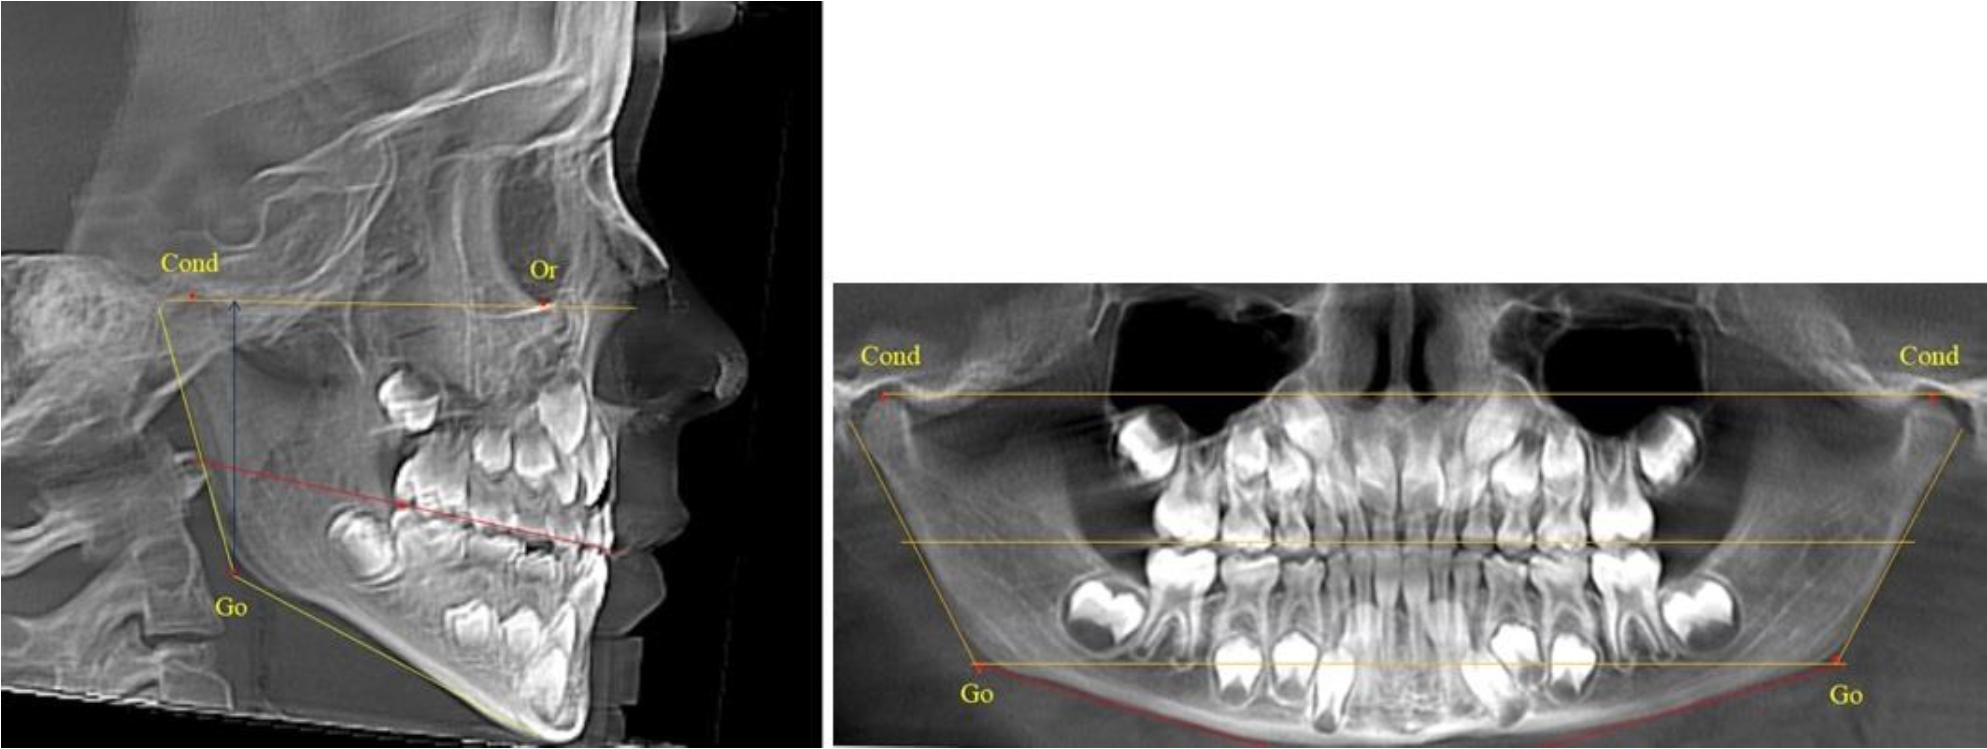

В 1-й группе были проанализированы 7 телерентгенограмм и 7 ортопантомограмм, что составило (6,60 ± 2,41) % от числа изученных рентгенограмм. На всех парах рентгенограмм угол нижней челюсти, измеренный на телерентгенограмме, соответствовал углу, полученному при построении угла на ортопантомограмме. Окклюзионная линия практически однотипно делила ветвь на два отдела (рис. 1).

Как на ортопантомограмме, так и на телерентгенограмме высота ветви у детей в периоде сформированного прикуса молочных зубов составляла (42,21 ± 2,48) мм. При этом высота верхней окклюзионно-суставной части была (22,57 ± 1,46) мм, а нижней – (19,64 ± 1,54) мм.

Учитывая вариабельность абсолютных величин, определи относительные показатели соразмерности частей ветви нижней челюсти. Так, отношение высоты верхней части ветви к нижней в среднем составляло 1,15 ± 0,13. Отношение общей высоты ветви к верхней ее части составляло 1,87 ± 0,14, а отношение общей высоты ветви к нижней ее части было 2,14 ± 0,16 и достоверных различий по относительному показателю отношения всей высоты к верхней и нижней челюсти нами не отмечено (р ˃ 0,05). При этом визуально обе части выглядели примерно равноразмерными.

Рис. 1. ТРГ и ОПТГ пациента 1-й группы

Рис. 2. ТРГ и ОПТГ пациента после прорезывания первых постоянных моляров